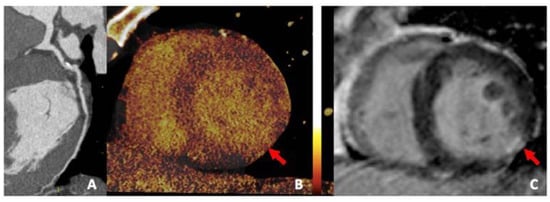

3.4. Iodine Perfusion Maps

- Mahnken, A.H.; Lautenschläger, S.; Fritz, D.; Koos, R.; Scheuering, M. Perfusion weighted color maps for enhanced visualization of myocardial infarction by MSCT: Preliminary experience. Int. J. Cardiovasc. Imaging 2008, 24, 883–890. [Google Scholar] [CrossRef] [PubMed]

- Bauer, R.W.; Kerl, J.M.; Fischer, N.; Burkhard, T.; Larson, M.C.; Ackermann, H.; Vogl, T.J. Dual-Energy CT for the Assessment of Chronic Myocardial Infarction in Patients with Chronic Coronary Artery Disease: Comparison with 3-T MRI. Am. J. Roentgenol. 2010, 195, 639–646. [Google Scholar]

- Rubinshtein, R.; Miller, T.D.; Williamson, E.E.; Kirsch, J.; Gibbons, R.J.; Primak, A.N.; McCollough, C.H.; Araoz, P.A. Detection of myocardial infarction by dual-source coronary computed tomography angiography using quantitated myocardial scintigraphy as the reference standard. Heart 2009, 95, 1419–1422. [Google Scholar] [CrossRef]

- Nakahara, T.; Toyama, T.; Jinzaki, M.; Seki, R.; Saito, Y.; Higuchi, T.; Yamada, M.; Arai, M.; Tsushima, Y.; Kuribayashi, S.; et al. Quantitative Analysis of Iodine Image of Dual-energy Computed Tomography at Rest. J. Thorac. Imaging 2018, 33, 97–104. [Google Scholar] [CrossRef] [PubMed]

- Carrascosa, P.M.; Deviggiano, A.; Capunay, C.; Campisi, R.; de Munain, M.L.; Vallejos, J.; Tajer, C.; Rodriguez-Granillo, G.A. Incremental value of myocardial perfusion over coronary angiography by spectral computed tomography in patients with intermediate to high likelihood of coronary artery disease. Eur. J. Radiol. 2015, 84, 637–642. [Google Scholar] [PubMed]

- Jin, K.N.; De Cecco, C.N.; Caruso, D.; Tesche, C.; Spandorfer, A.; Varga-Szemes, A.; Schoepf, U.J. Myocardial perfusion imaging with dual energy CT. Eur. J. Radiol. 2016, 85, 1914–1921. [Google Scholar]

- Delgado Sánchez-Gracián, C.; Oca Pernas, R.; Trinidad López, C.; Santos Armentia, E.; Vaamonde Liste, A.; Vázquez Caamaño, M.; Tardáguila de la Fuente, G. Quantitative myocardial perfusion with stress dual-energy CT: Iodine concentration differences between normal and ischemic or necrotic myocardium. Initial experience. Eur. Radiol. 2016, 26, 3199–3207. [Google Scholar]

- Ruzsics, B.; Lee, H.; Zwerner, P.L.; Gebregziabher, M.; Costello, P.; Schoepf, U.J. Dual-energy CT of the heart for diagnosing coronary artery stenosis and myocardial ischemia-initial experience. Eur. Radiol. 2008, 18, 2414–2424. [Google Scholar] [PubMed]